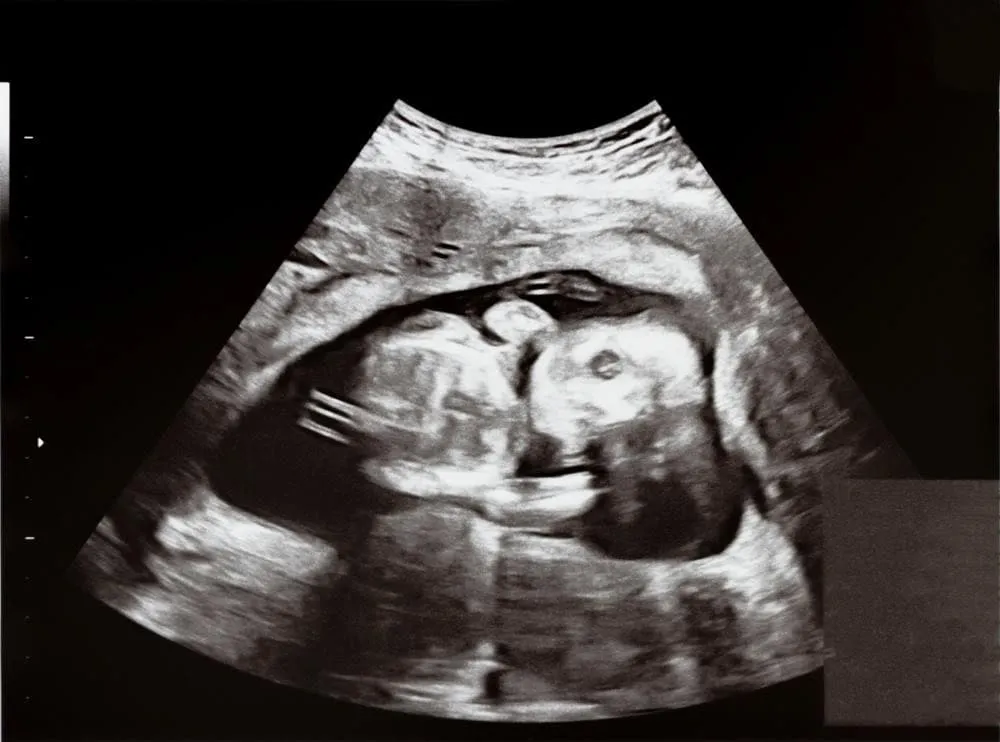

Hình ảnh siêu âm thai nhi 17 tuần tuổi.